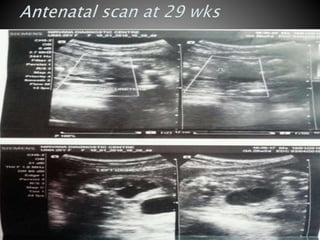

 USG scan at 29 weeks s/o bilateral fetal moderte to severe

hydronepro ureterosis ((LT>RT) with thickened urinary mucosa

s/o bladder outlet obstruction. RT kidney 3cm x1.6cm. Lt kidney

3.8cmx 2.6cm.